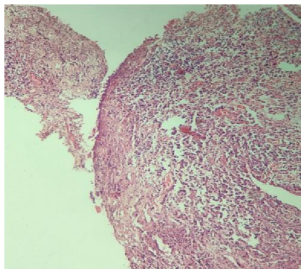

On histopathological examination pseudostratified ciliated columnar epithelium with underlying fibro collagenous connective tissue, infiltrated with dense chronic inflammatory cells predominantly comprising lymphocytes and plasma cells were seen. Numerous dilated and engorged capillaries lined with extravasated red blood cells were observed, which were suggestive of chronic inflammation (Fig.3).

Figure 3: Histopathological examination at 10x magnification revealed fibro collagenous tissue interspersed with a dense infiltrate of chronic inflammatory cells

Figure 3